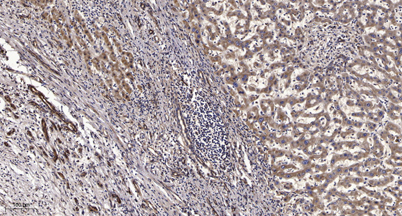

Immunohistochemical analysis of paraffin-embedded human liver cancer. 1, Antibody was diluted at 1:200(4° overnight). 2, Tris-EDTA,pH9.0 was used for antigen retrieval. 3,Secondary antibody was diluted at 1:200(room temperature, 45min).